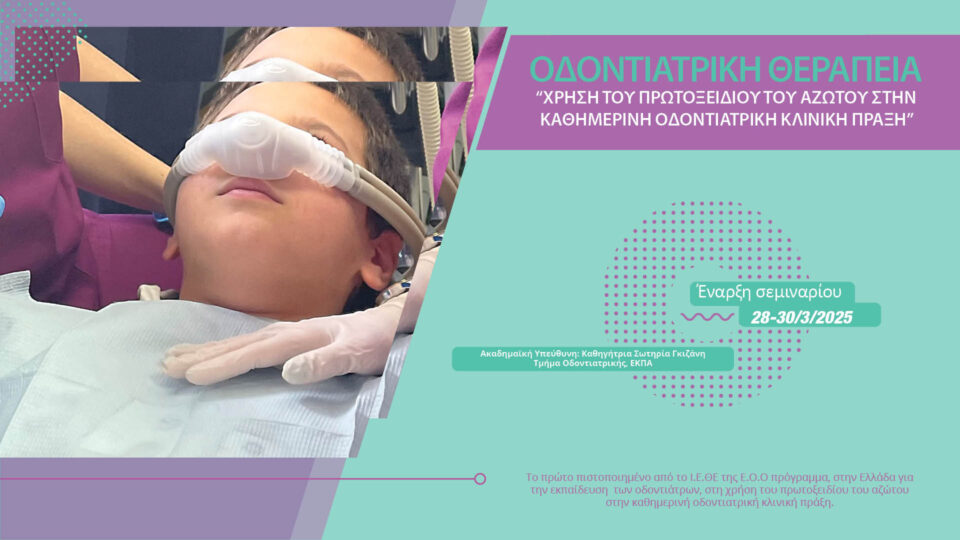

Άμεση κατευθυνόμενη τοποθέτηση εμφυτεύματος σε μετεξακτικό φατνίο στην αισθητική ζώνη. Θεραπευτικές προσεγγίσεις από το βιολογικό υπόβαθρο στο live surgery.

Παρουσίαση του συστήματος εμφυτευμάτων Omni taper.

Οι υψηλές αισθητικές απαιτήσεις της σύγχρονης οδοντιατρικής καλούν για πλήρη αποκατάσταση της αρμονίας ανάμεσα σε μαλακούς και σκληρούς ιστούς, αλλά και ανάμεσα στο χαμόγελο και όλο το πρόσωπο.

Η αποκατάσταση αλλά και η διατήρηση των μαλακών και σκληρών ιστών στην αισθητική ζώνη εξαρτάται από πάρα πολλούς παράγοντες που έχουν να κάνουν από την επιλογή χειρουργικής προσέγγισης μέχρι και τα χαρακτηριστικά της προσθετικής αποκατάστασης και του εμφυτεύματος.

Στο περιστατικό που θα αντιμετωπιστεί live θα γίνει άμεση τοποθέτηση εμφυτεύματος με πλήρη καθοδήγηση χειρουργικού νάρθηκα, θα συζητηθούν οι εναλλακτικές προσεγγίσεις και θα παρουσιαστεί ο τρόπος και τα διαφορετικά σενάρια εξατομίκευσης της επούλωσης των μαλακών ιστών.